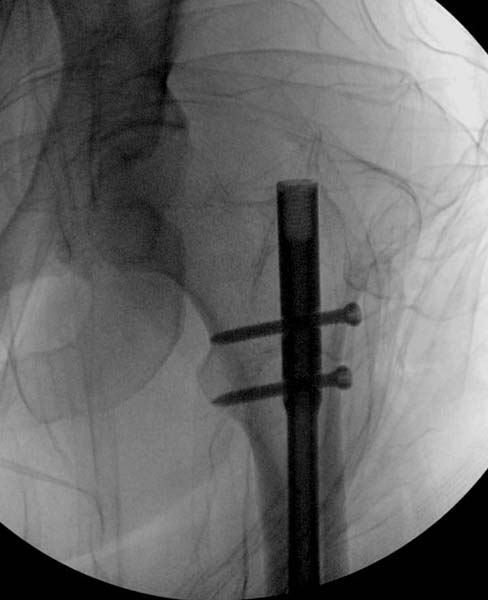

> стабильная.. На третьий день провели стабилизацию перелома бедра

> антеградным остеосинтезом.

> Закрытый БИОС решает множественные проблемы связанные с лечением

> переломов, но проблема дистальной блокировки без рентгена до сих пор

> остается нерешенной. Рекламированные производителями приспособления для

> дистальной блокировки из-за различной кривизны кости не эффективны или

> стоит очень дорого (Smith&Nephew SureLock). Задержка операции из-за

> блокировки не всегда удовлетворяет, и многих вынуждает искать

> альтернативные методы фиксации. С результатами таких действий,

> остеомиелитом и несращениями, встречаемся в ежедневной жизни..

> Для решения проблемы дистальной блокировки компания DigiMed недавно

> предложила систему блокировки без рентгена. Пока в стране только два набора

> и только для антеградных гвоздей, но компания работает над созданием

> устроиства для других гвоздей тоже..

> Результат первых случаев показала отсутствие разницы между занятиями на

> муляжах, а также Workshop и с удивительной точностью вывел латерально над

> кожей специальное сверло. Дальше по сверлу тонкий направитель и проводится

> сверление каннюлированным сверлом....